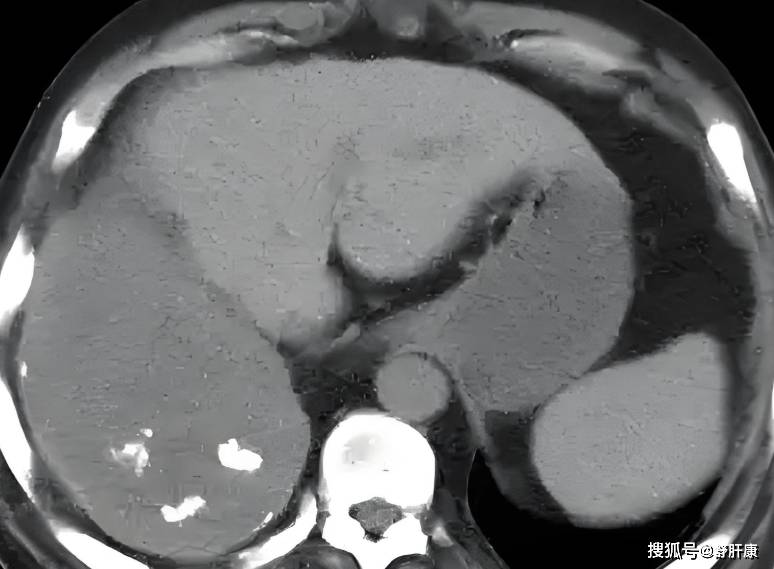

肝右叶钙化灶是什么?

肝右叶钙化灶是指在肝脏右叶区域出现的钙质沉积,通常在影像学检查如B超CT中表现为边界清楚密度较高的亮点或阴影其本质是局部组织因钙盐沉积形成的稳定结构,多数情况下为良性病变形成原因多样,主要包括肝内胆管结石胆管内结石长...